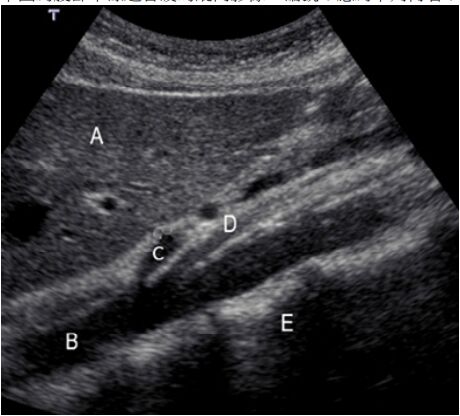

71.下圖為腹部中線超音波的縱向影像,編號 C 應為下列何者?

(A)aorta (B)celiac trunk (C)inferior vena cava(IVC) (D)superior mesenteric artery(SMA)